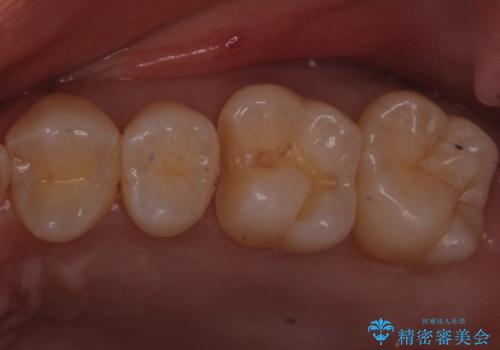

歯と歯の間の虫歯 ゴールドインレーでの修復

- フロスがよく詰まるところがあるとのことで来院されました。

検査の結果、左上の奥歯に虫歯があることが確認されました。

見た目よりも精度を優先したいとのことだったため、ゴールドインレーでの修復処置を行いました。

ゴールドの修復物は高い精度を出すことができるため非常に適合の良いものを装着することができます。